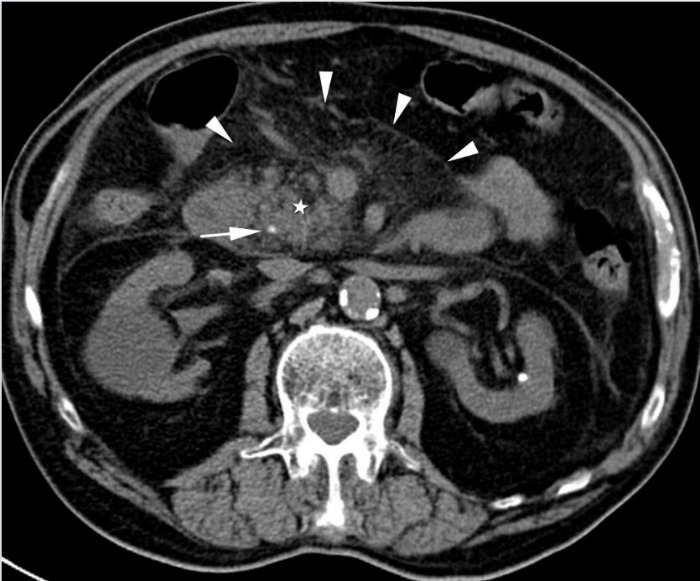

На КТ поджелудочной железы при травмах OIS I и II степени проявляются слабо контурирующие «потухшие» участки на фоне нормальной паренхимы или очаговое или диффузное расширение поджелудочной железы. Незначительная контузия (I степень) (изображение 1) включает одну анатомическую область поджелудочной железы, при II степени травмы (изображение 2) задействуется более одной анатомической области поджелудочной железы.

Изображение 1. Сорокадвухлетний мужчина с травмой поджелудочной железы. Изображение показывает небольшую гиподенсную область в передней части головки поджелудочной железы (стрелка), указывая на травму I степени.

Разрывы поджелудочной железы, наблюдаемые при III (изображение. 3) и IV (изображение 4) степенях, представляют собой линейные расщелины, перпендикулярные длиннику поджелудочной железы и заполненные жидкостью или кровью (изображение 5). Если есть четкое разделение паренхимы, возможно, присутствует разрыв поджелудочной железы. Наиболее распространенным местом разрыва поджелудочной железы является тело или головка поджелудочной железы. Поверхностные образования включают менее 50 % толщины железы, в то время как разрывы включают более 50 % железы и имеют высокую частоту сопутствующих травм. Разрыв поджелудочной железы может быть пропущена или недооценен даже при МСКТ из-за наложения фрагментов разрыва.

Изображение 3. 30-летняя женщина получила травму живота во время ДТП. Изображение МСКТ показывает линейный гиподенсный участок перпендикулярно длиннику поджелудочной железы в области хвоста (белая стрелка), что указывает на разрыв хвоста III степени.

Изображение 4. 55-летний мужчина после удара бейсбольной битой по животу. На МСКТ-снимке (А) обнаружена большая рваная рана головки поджелудочной железы (стрелка), затрагивающая более 50 % толщины паренхимы и указывающая на высокую вероятность повреждения протока.

На магнитно-резонансной холангиопанкреатографии (В) у того же пациента подтверждается повреждение протока (стрелка).

Изображение 5. Разрыв поджелудочной железы IV степени у 41-летнего мужчины, пострадавшего в результате ДТП. На МСКТ (А) показан линейный разрыв (стрелка) в головке поджелудочной железы справа от верхней брыжеечной вены.

На МРТ (В) изображение того же пациента демонстрирует разрыв в головке поджелудочной железы (стрелка).

(Слева) На аксиальной КТ с контрастным усилением определяется гиподенсный участок (разрыв) в средних отделах тела поджелудочной железы. Обратите внимание на небольшое количество жидкости позади поджелудочной железы поблизости от селезеночной вены.

(Справа) На аксиальной КТ с контрастным усилением у этого же пациента на более каудальном уровне также определяется разрыв поджелудочной железы; жидкость возле ее края становится более очевидной. У некоторых пациентов наличие жидкости позади поджелудочной железы является наиболее очевидным признаком ее разрыва.

3. КТ признаки травмы поджелудочной железы:

• Даже при отсутствии дискретного очага контузии или разрыва обычно обнаруживаются вторичные признаки повреждения поджелудочной железы или посттравматического панкреатита:

о Инфильтрация перипанкреатической клетчатки (отсутствие визуализации нормальных жировых пластинок) и жидкость около края поджелудочной железы:

- Наличие жидкости между поджелудочной железой и селезеночной веной является чувствительным (60-90%) признаком повреждения поджелудочной железы